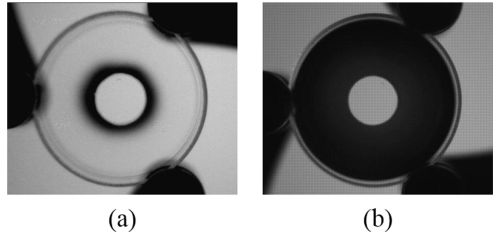

The new system relies on a simple aperture filter that consists of a disk-shaped region in the middle and a ring-shaped area on the outside. The middle area lets in visible and NIR light, but the outer ring only permits NIR light. When you place the filter in the imaging system, the aperture is wide enough to let in plenty of NIR light. But since visible light can't penetrate the outer ring, the visible-sensitive part of the filter has a small enough aperture that the depth of field is large.